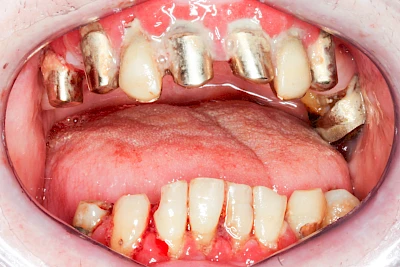

Ist zunächst nur das Zahnfleisch von der Entzündung betroffen, spricht man von Gingivitis. Später, wenn auch der Knochen um die Zähne herum entzündet ist, spricht man von einer Parodontitis. Bei der Parodontitis wird der Knochen nach und nach abgebaut und das Zahnfleisch zieht sich zurück. Die Zahnhälse und Zahnwurzeloberflächen liegen mehr und mehr frei. Die Zähne werden zunehmend lockerer und fallen schließlich aus.

Bei Implantaten – also operativ eingebrachten künstlichen Zahnwurzeln – kann der Körper die Bakterien auch nicht so gut abwehren. Hier spricht man im Fall einer Entzündung von einer Peri-Implantitis, also einer Entzündung um das Implantat herum.